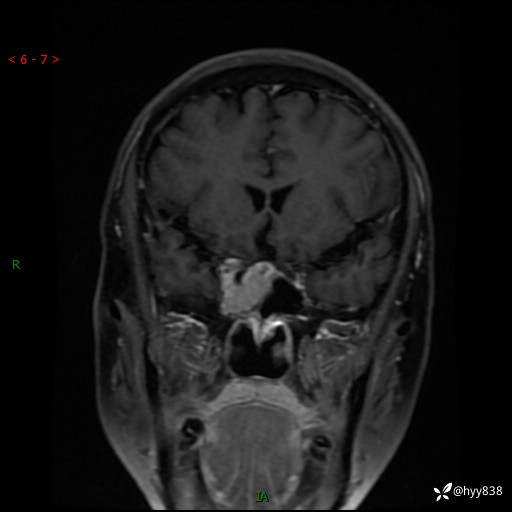

规培和研究生教学片:鞍旁占位,脑膜瘤 VS 侵袭性垂体瘤---结果公布~

MRI增强(外院平扫)